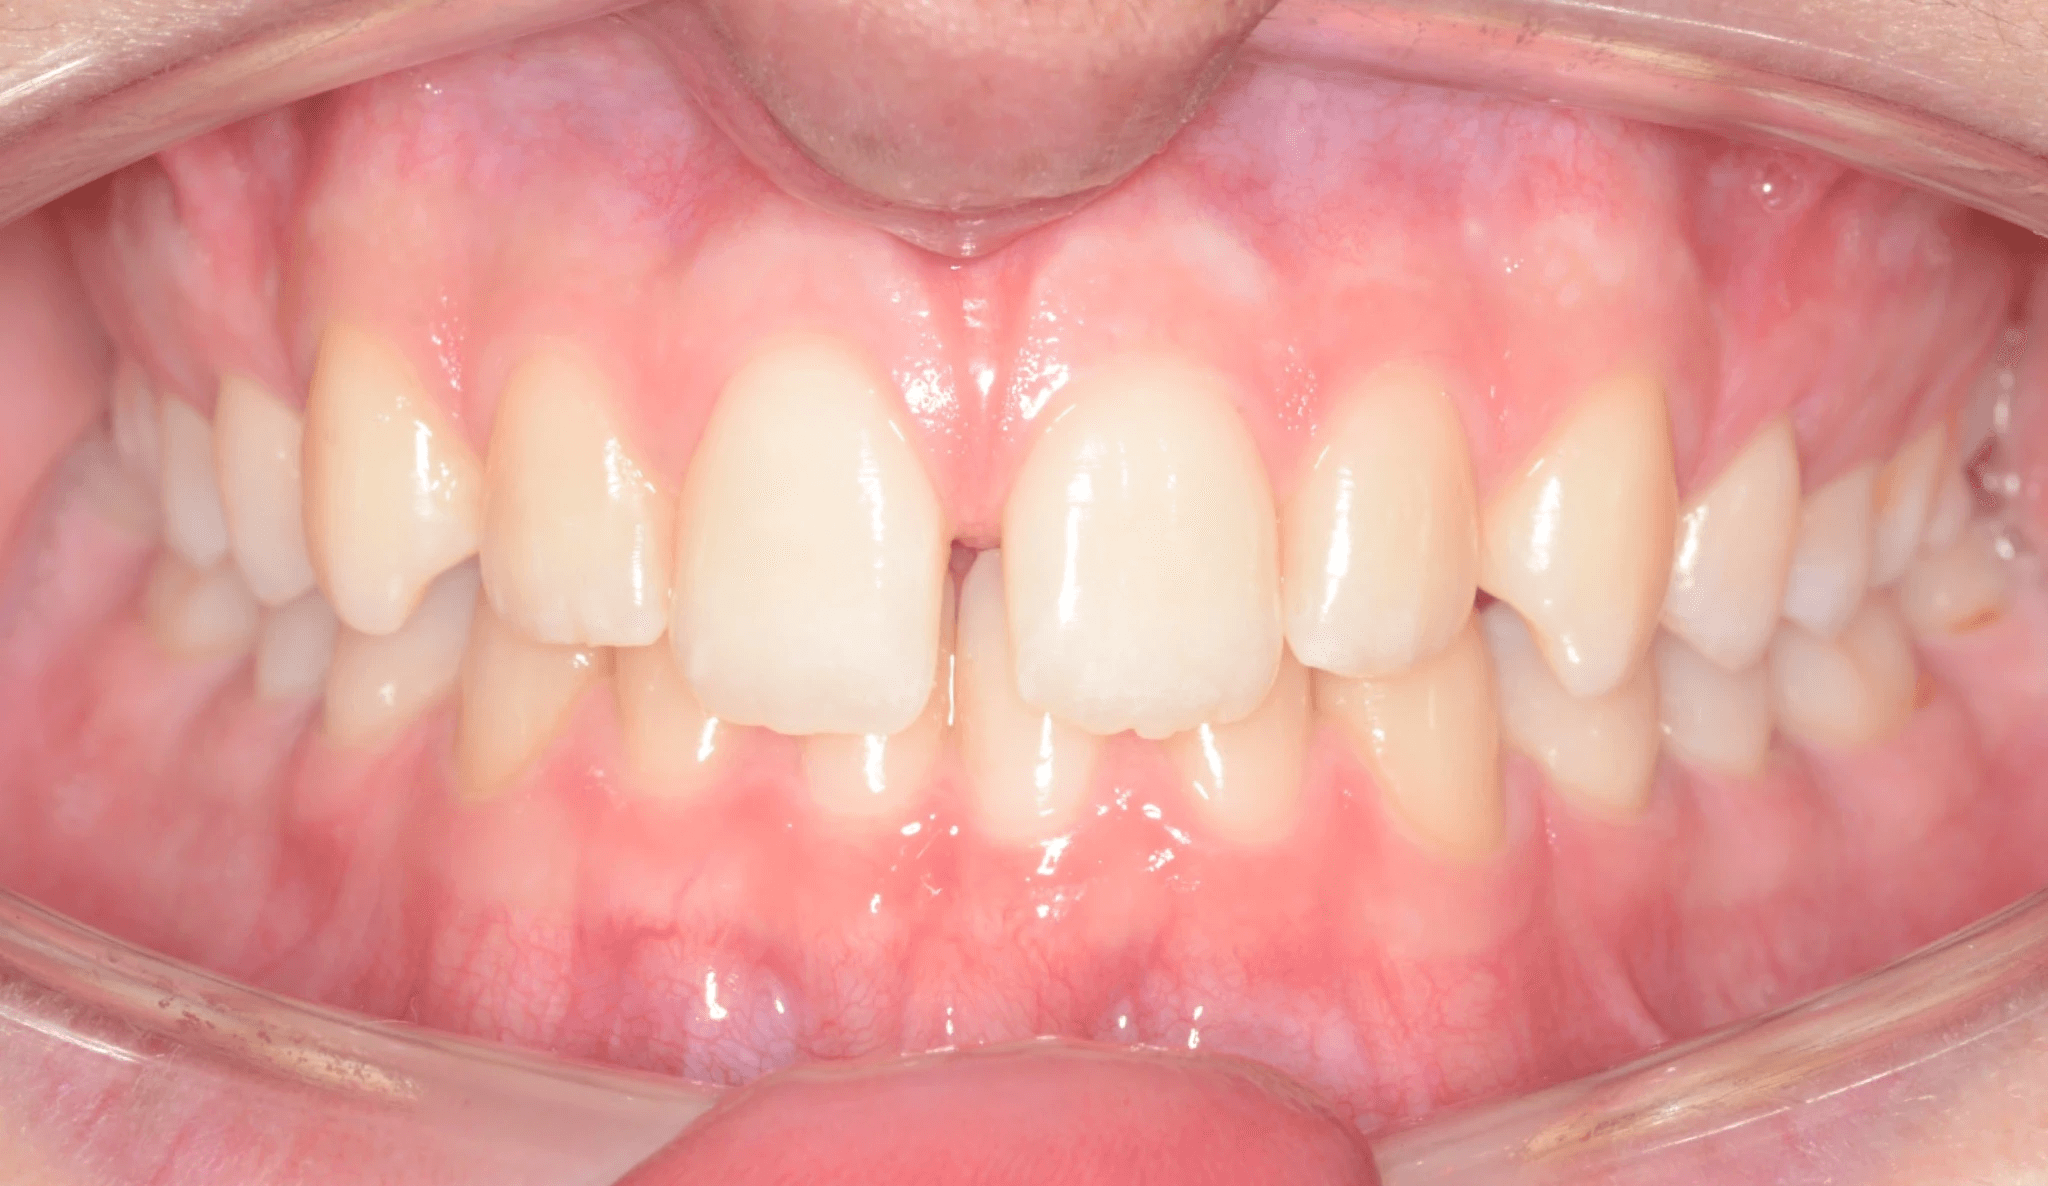

Initial treatment

INTRAORAL